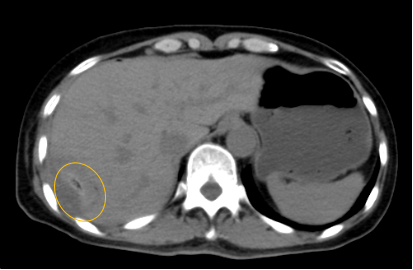

入院后,影像診療中心立即給李女士完善了CT和MR檢查,發(fā)現(xiàn)病變位于肝包膜下,臨近膈肌,消融治療過程中有并發(fā)損傷膈肌的可能,難度較大,但是采用精準(zhǔn)影像定位是可以完成的。陳寶瑩主任立即與腫瘤三病區(qū)劉金鵬主任聯(lián)系,并與影像微創(chuàng)治療小組進(jìn)行MDT討論:患者為卵巢癌肝右葉包膜下單發(fā)轉(zhuǎn)移瘤,最長徑不超過3cm,患者對局部治療的主觀愿望強烈,符合消融治療專家共識,遂制定了影像引導(dǎo)下局部消融治療聯(lián)合全身治療的綜合治療方案。

針對這個特殊部位的腫瘤,要想消融完全,那么膈肌損傷的風(fēng)險就很高,陳寶瑩主任帶領(lǐng)影像微創(chuàng)亞專業(yè)組成員仔細(xì)閱讀CT圖像,設(shè)計進(jìn)針路徑,結(jié)合MR圖像確定腫瘤活性范圍,制定了周密而詳盡的消融計劃。臘月二十九,即住院第二天影像微創(chuàng)治療小組圓滿為患者完成了腫瘤微波消融治療,觀察24小時后出院回家過年。術(shù)后48小時隨訪患者無明顯不適,術(shù)后7天隨訪,患者肝功、血常規(guī)等各項指標(biāo)均恢復(fù)正常。